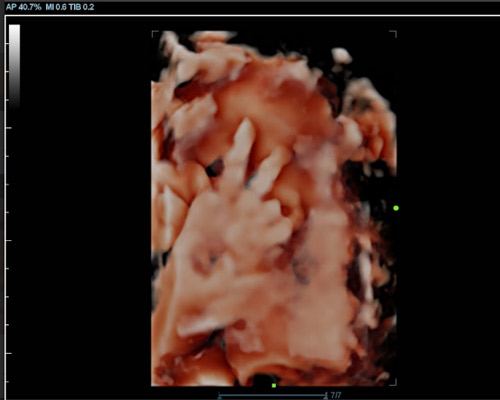

A 3D scan produces detailed still images that show the baby’s face and body in three dimensions. A 4D baby scan near Nottingham goes a step further by displaying those images in motion, allowing parents to see their baby move, stretch, or even smile.

- Real-Time Movement - The scan allows you to watch your baby move, stretch, or yawn during the session.